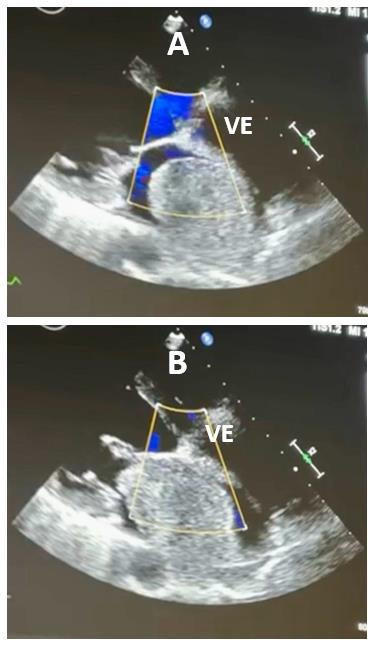

Mulher de 44 anos, portadora de hipertensão arterial controlada com losartana, sem outras comorbidades conhecidas, refere dispneia progressiva há cerca de 4 meses. Relata dificuldade de realizar suas caminhadas habituais devido à dispneia e à poliartarlgia de membros inferiores. Nega dor torácica, mas evoluiu com episódio de síncope após subir rapidamente dois lances de escadas há cerca de 2 semanas. Apresenta também dificuldade recente de dormir sobre seu lado esquerdo, devido à sensação de “sufocamento”.

Ao exame: Lúcida, orientada, emagrecida (perda de 10kg em 3 meses), acianótica, corada. Temp: 37,2°C. FC: 102 bpm, PA: 100x64 mmHg, SatO2: 96%. MVUA com crepitação fina nas bases. Ritmo cardíaco regular, em 2T, BNF, com ruído protodiastólico de baixa frequência audível no foco mitral em decúbito lateral esquerdo, seguido de um sopro diastólico 2+/6+ no mesmo foco. Abdome e MMII sem alterações. ECG com taquicardia sinusal. Ecocardiograma transtorácico revelou as imagens A e B abaixo.

Considerando as duas imagens ecocardiográficas, assinale a opção que provavelmente corresponde ao ruído protodiastólico de baixa frequência descrito no exame físico.